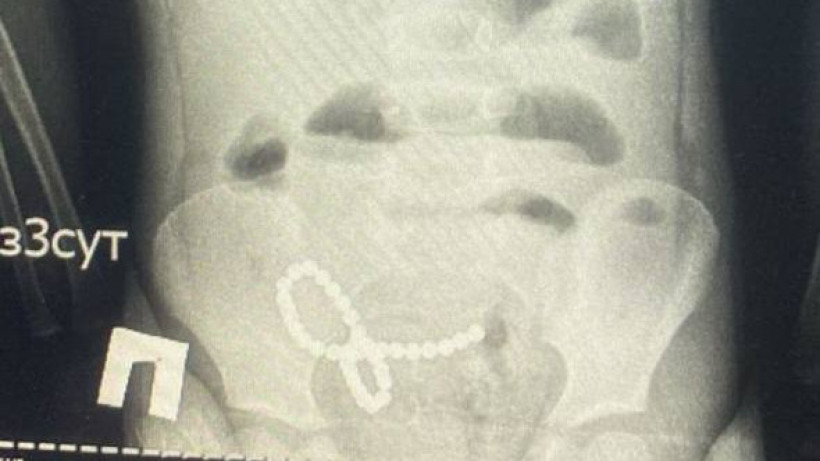

Фото: Денсаулық сақтау министрлігі

Денсаулық сақтау министрлігінің мәліметінше, 2 қаңтарда науқас шұғыл түрде Зерендіден балалар ауруханасына жеткізілген. Жағдайы күрт нашарлаған баланың іші қатты ауырсынып, қайта-қайта лоқсығарн. Рентген аппаратымен   тексеру кезінде науқастың ішегінен көптеген бөгде заттар анықталған.

Баланың тоқ ішегі мен аш ішегі зақымдалып, перфорация мен перитонит тудыратын 39 магниттік шарик болды. Бөгде заттарды алып тастау және оның салдарын жою ауыр зақымдануға байланысты күрделене түсті,-деді дәрігер.